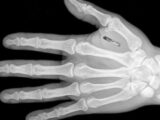

マイクロチップは直径約2mm、長さが約12mmの円筒形で、電子標識をガラスカプセルで包んだ小さな器具だ。獣医師に皮下に埋め込んでもらわなければならないが、一般的な皮下注射と変わらず、動物たちへの負担はほとんどないとされている。すでに迷子対策として自主的に埋め込んでいる飼い主は多いだろう。

だが、逆にマイクロチップに反対する人々もいる。犬の情報サイト「Dogs Naturally」では、英国小動物獣医協会(BSAVA)の研究を取り上げている。この研究によれば、マウス実験でマイクロチップに発ガン性があったことや、世界各地でマイクロチップを埋められた動物にガンが確認されているというのだ。また、マイクロチップ埋め込み手術でペットが死亡した事例や、マイクロチップで神経を傷つけられて障害が起きたケース、またマイクロチップが移動してしまった例もあるとし、その危険性を訴えている。